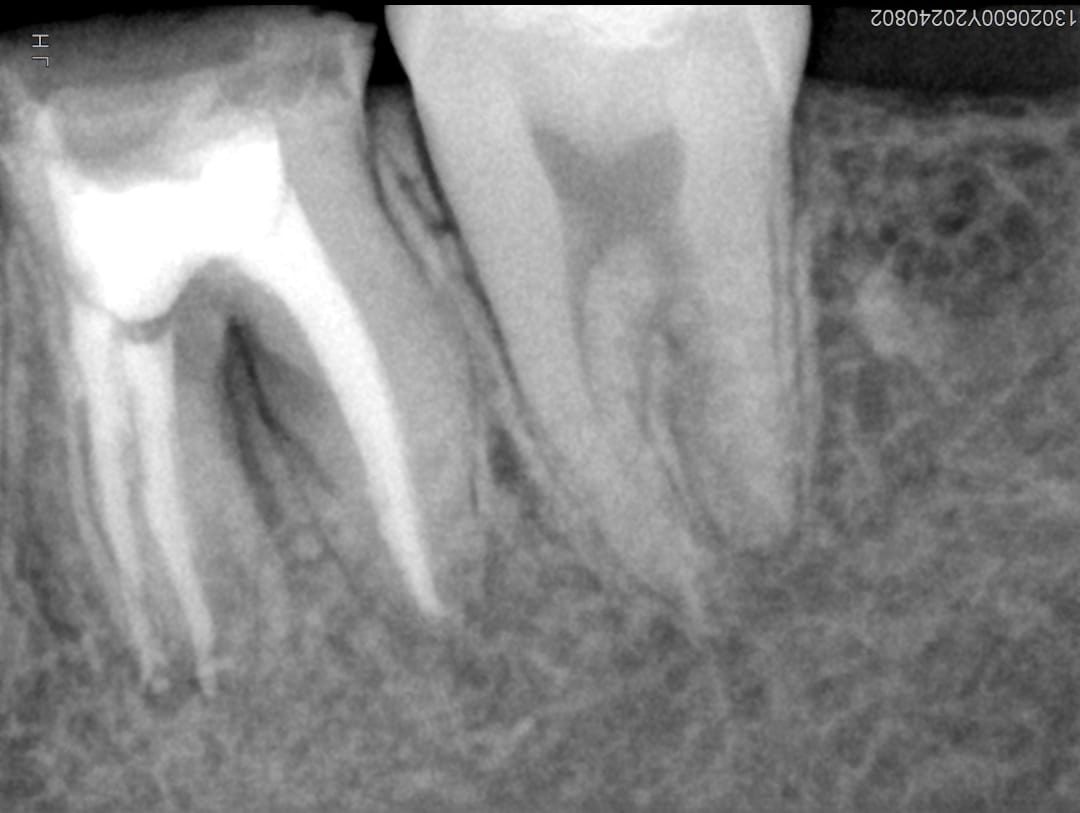

Veja alguns casos de sucesso